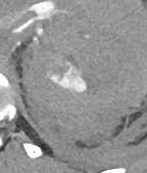

| Grade | Description | Image | CT |

| III |

|

||